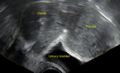

A small uterine fibroid seen within the wall of themyometrium on a cross sectional ultrasound view |

While a bimanual examination typically can identify the presence of larger fibroids, gynecologic ultrasonography (ultrasound) has evolved as the standard tool to evaluate the uterus for fibroids. Sonography will depict the fibroids as focal masses with a heterogeneous texture, which usually cause shadowing of the ultrasound beam. The location can be determined and dimensions of the lesion measured. Also magnetic resonance imaging (MRI) can be used to define the depiction of the size and location of the fibroids within the uterus.